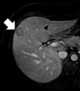

Liver lesion with central scar